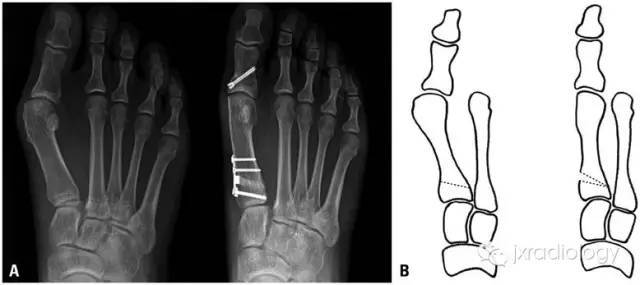

手术治疗1974 年Helal等列出了130种治疗踇外翻的手术方法,随后增至200 余种value币。踇外翻的疗效尚无统 一的评定标准。常用是近端截骨术(下图)该术适用于中度或重度畸形。

骨干截骨术(下图)value币。